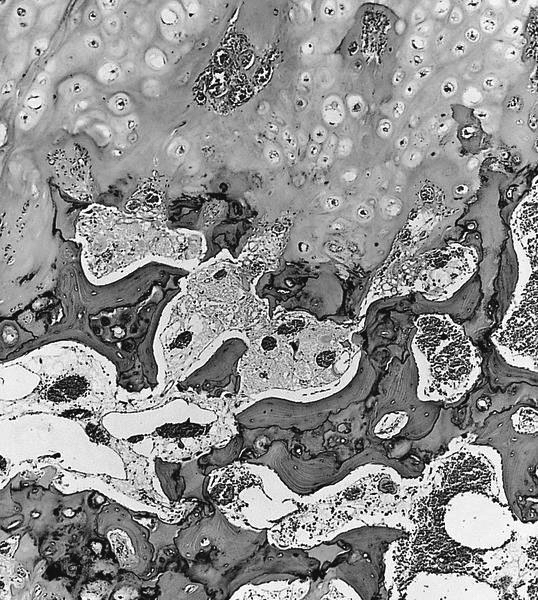

Microscopic (histologic) description

- Cap composed of mature hyaline cartilage with overlying fibrous perichondrium

- In young patients, transition between bone and cartilage cap resembles growth plate, showing endochondral ossification into mature bone; cartilage cap diminishes and may essentially be absent in older adults

- Marrow elements may be present within bony stalk; marrow space / cancellous bone contiguous with that of the native bone

Microscopic (histologic) images